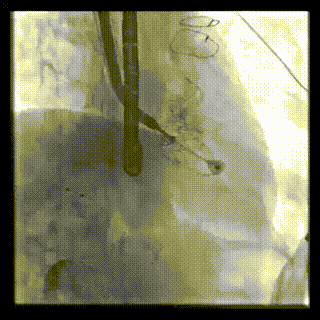

2021年12月24日,復(fù)旦大學(xué)附屬中山醫(yī)院葛均波院士團(tuán)隊(duì)成功應(yīng)用LuX-Valve Plus為一例極重度三尖瓣反流(TR)合并房顫、房缺的患者完成了經(jīng)血管三尖瓣置換術(shù),這是在前基礎(chǔ)上,本周完成的第三例經(jīng)血管三尖瓣置換手術(shù),葛均波院士、周達(dá)新教授等與心外科魏來教授、賴顥教授,心超室的潘翠珍教授、李偉教授及麻醉科的郭克芳教授共同完成了本周手術(shù),均獲得圓滿成功!患者術(shù)后超聲顯示無TR,臨床癥狀明顯改善。本周手術(shù)的成功也為LuX-Valve Plus救治性臨床研究添上了濃墨重彩的一筆。

本周三例接受LuX-Valve Plus經(jīng)血管三尖瓣置換術(shù)的患者中,第一例患者為冠狀動(dòng)脈旁路移植術(shù)+Bentall+二尖瓣成形術(shù)后;第二例患者為永久起搏器植入術(shù)后,存在跨三尖瓣導(dǎo)線;第三例患者合并房顫、房缺及左心耳封堵術(shù)后。

三例患者入院后,葛均波院士團(tuán)隊(duì)周達(dá)新教授、潘文志教授、張?jiān)床┦俊㈥惿┦考靶某业呐舜湔浣淌?、李偉教?/strong>對(duì)患者的情況進(jìn)行詳細(xì)評(píng)估和討論,最終決定為三例患者選擇LuX-Valve Plus40mm、50mm和50mm型號(hào)的瓣膜進(jìn)行手術(shù)治療。手術(shù)后即刻拔除氣管插管,術(shù)后患者三尖瓣反流癥狀得到顯著改善,復(fù)查心超結(jié)果顯示人工三尖瓣瓣膜支架固定穩(wěn)定,瓣葉關(guān)閉形態(tài)未見異常,未見明顯反流。